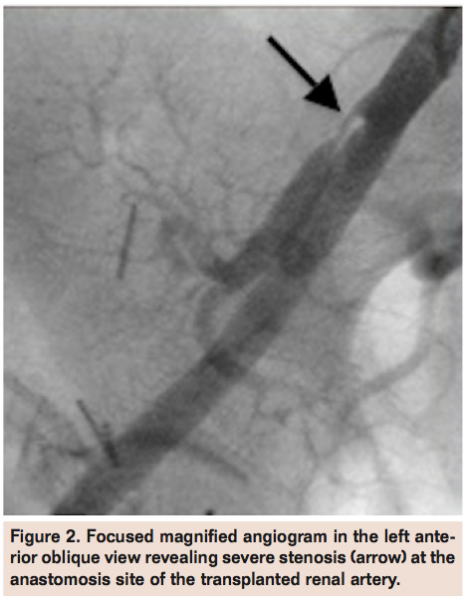

However, it was not until selective right external iliac artery angiogram from the left common femoral artery in the left anterior oblique view was performed that a significant stenosis of the TRA at the anastomosis site was visualized (Figure 2). An 8 Fr MP guide was used to selectively engage the TRA and a guidewire advanced across the lesion into the distal vessel (Figure 3). After predilation with a compliant balloon, an Express 5 mm x 16 mm stent (Boston Scientific) was deployed and post-dilated using a 6 mm x 20 mm balloon with excellent angiographic result and brisk flow (Figure 4).